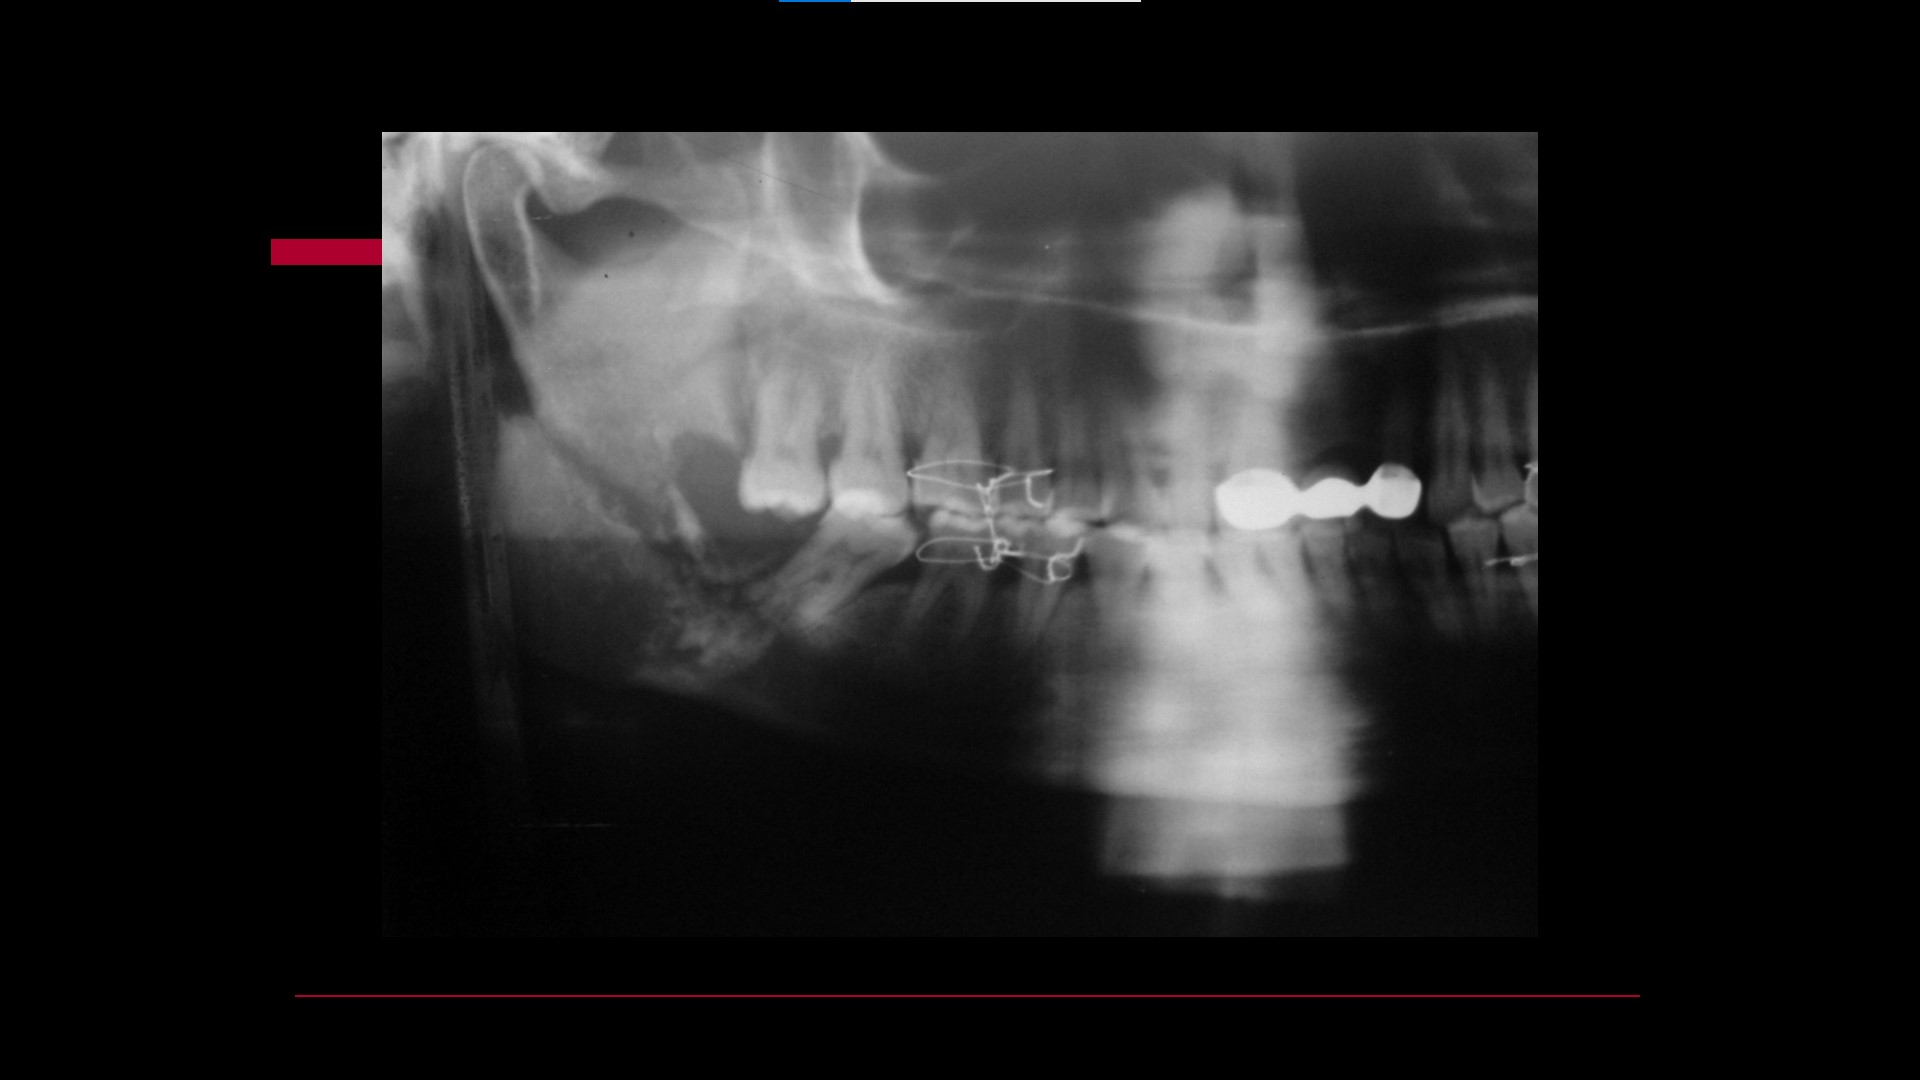

Impacted teeth

Oral Surgical Procedures

Relationship between Fractures of Mandibular Angle and the Presence of a Lower Third Molar